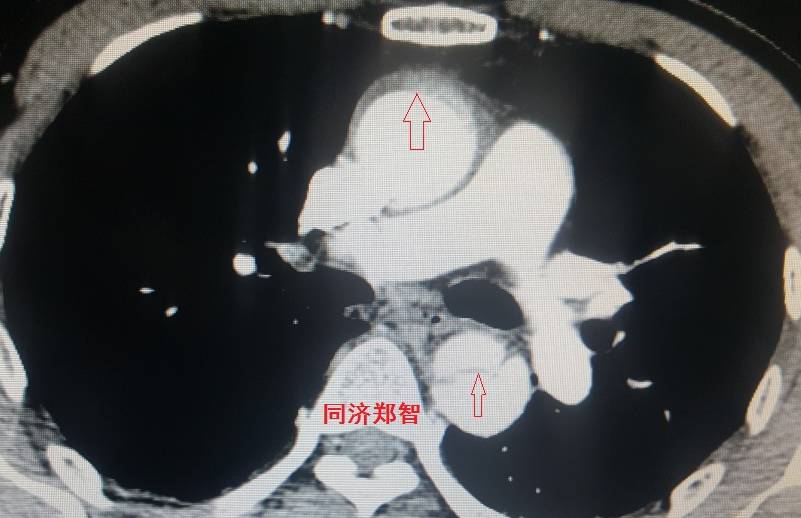

病例五

平扫CT提示主动脉弓层面及右肺动脉层面均可见主动脉血管腔内的内膜片影(红色箭头所示),CTA显示为A型主动脉夹层。